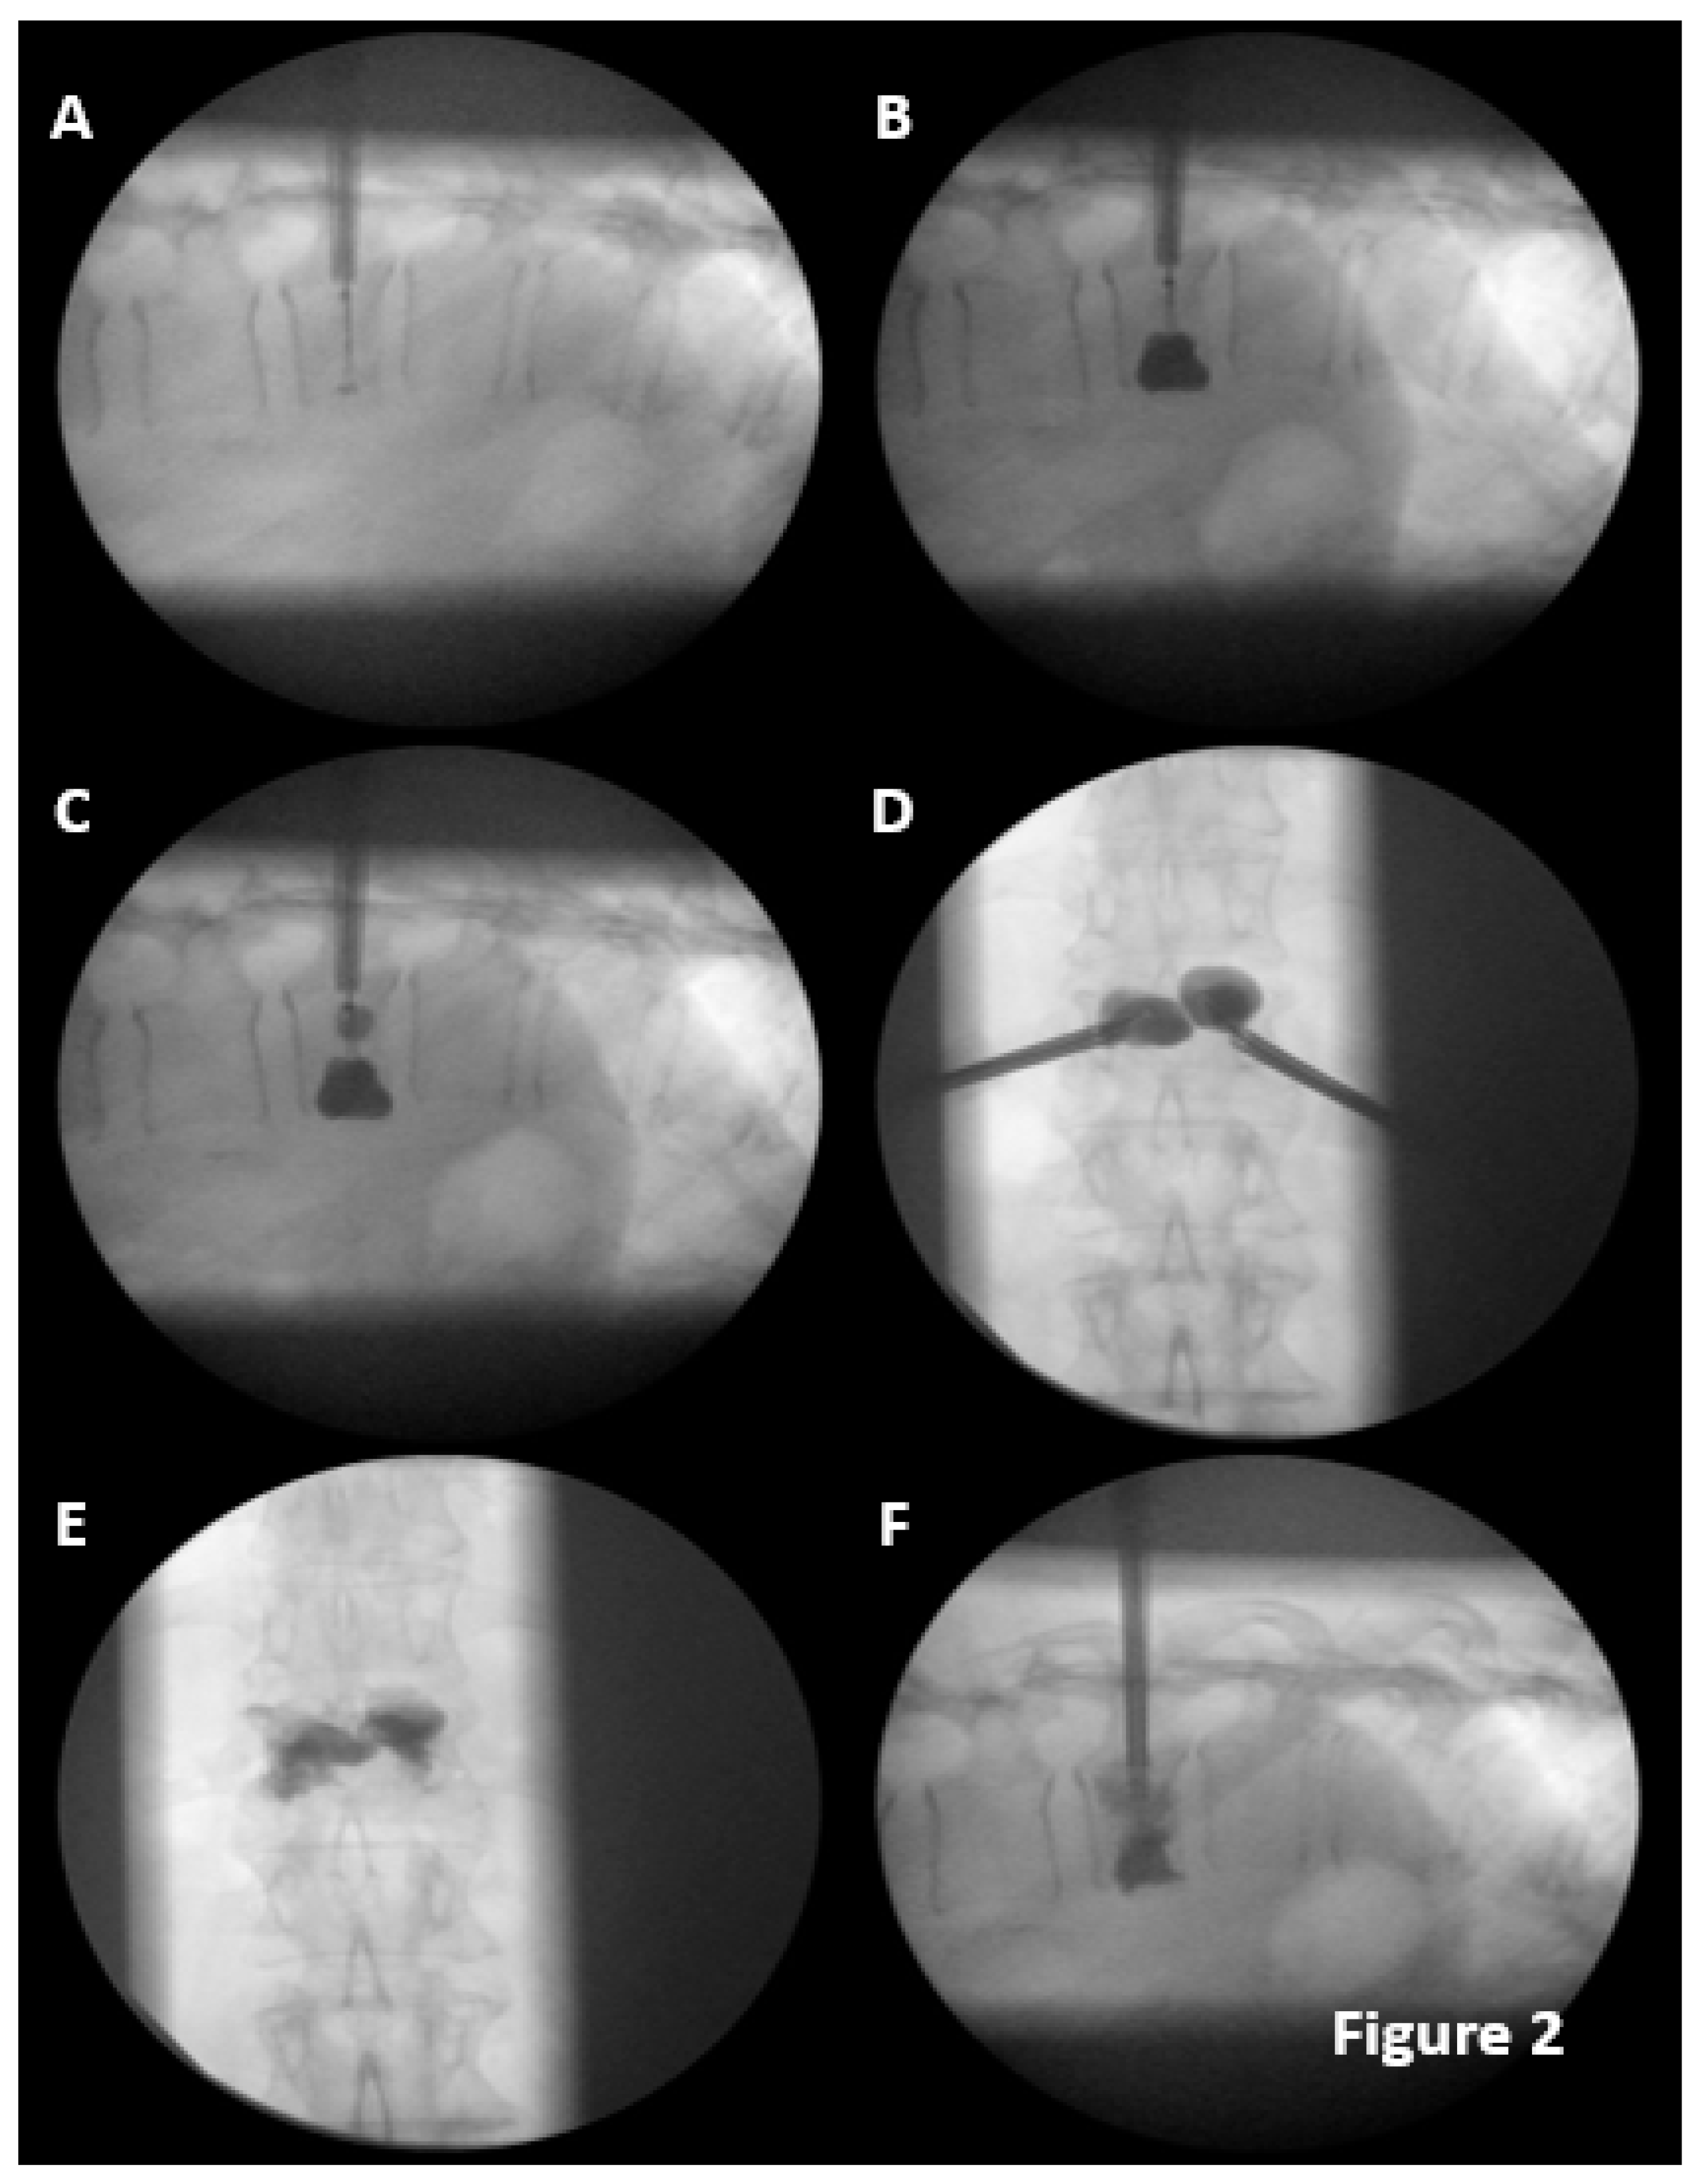

The vertebral reconstruction procedure by balloon kyphoplasty was performed as follows: a simple (Figure 1) or double (Figure 2) 8mm balloon was introduced for each vertebral pedicle.

Figure 1. Kiphoplasty single balloon procedure in two levels. A. Cannulas inserted in vertebral body. B. The balloons were inflated and this reduced the fractures. Lateral projection C. B in anteroposterior projection. D. Cemented vertebrae in lateral projection. E. D in anteroposterior projection.